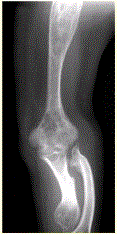

问题 患者男,22岁,长期存在骨和关节变形,近期出现右肘关节疼痛,进行性加重。行右肘关节X线正侧位片检查,见下图。 有关内生软骨瘤(Ollier病),描述正确的是

选项 A.不属于遗传性病变 B.不伴发其他病变 C.常见于女性青少年 D.出现关节疼痛进行性加重对诊断无重要意义 E.伴发软骨发育障碍 F.具有单侧发病倾向

答案 AEF